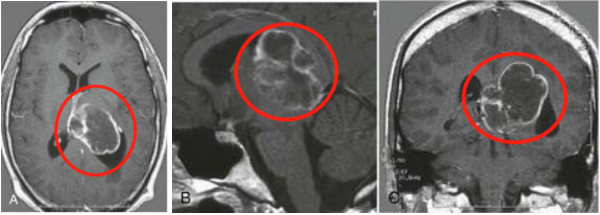

一名70歲女性一次出現(xiàn)枕部進(jìn)行性頭痛的病史長達(dá)四年。她將自己的頭痛描述為咳嗽或打噴嚏時加劇的壓力感。在過去的兩年里頭痛愈發(fā)嚴(yán)重。由于這些發(fā)現(xiàn),她接受了腦部核磁共振成像檢查,顯示右側(cè)下斜坡腦膜瘤延伸穿過頸靜脈結(jié)節(jié)的頂部,并突出到枕骨大孔的前唇(圖1A,1B)。腫瘤測量為37.1毫米斜矢狀,19.5毫米高,35.1毫米斜冠狀。延髓向后推,小腦扁桃體受壓。右側(cè)椎動脈包裹在枕骨大孔處。沒有腦積水的跡象。

圖1:(A)診斷時大腦的軸向和(B)冠狀面磁共振成像顯示右側(cè)下斜坡腦膜瘤。

由于腫瘤的復(fù)雜性及其對基本結(jié)構(gòu)(腦干、腦神經(jīng))的影響,以及梗阻性腦積水的高發(fā)展風(fēng)險,在醫(yī)療隊的推動下,在三個不同的省份進(jìn)行了多次咨詢。其中包括對高度化放射治療技術(shù)的神經(jīng)外科意見。特別是,有一個初步咨詢神經(jīng)外科,轉(zhuǎn)介到另一個省的伽瑪?shù)斗派渫饪疲D(zhuǎn)介到另一個神經(jīng)外科醫(yī)生的二個意見,轉(zhuǎn)介和放射腫瘤小組的工作,主張尋求省外的神經(jīng)外科意見,然后開始外射束放射治療。全部的咨詢都建議采用傳統(tǒng)的體外放射治療。三位神經(jīng)外科醫(yī)生將病人轉(zhuǎn)介到省外的另一個放射腫瘤學(xué)項目。在計劃進(jìn)行核磁共振成像時,腫瘤測量到42.3毫米的斜矢狀面,21.1毫米的高度和38.8毫米的斜冠狀面(圖2A,2B)。此后不久開始體外放射治療。獲得多種意見的過程持續(xù)了大約12個月。

圖2:(A)治療計劃時大腦的軸向和(B)冠狀面磁共振成像顯示右側(cè)下斜坡腦膜瘤。